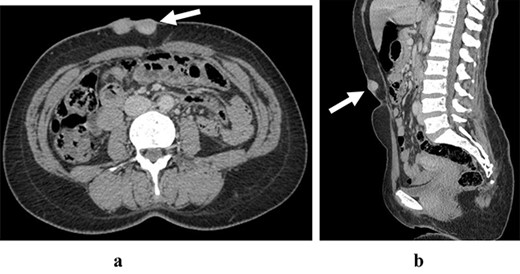

A 45-year-old woman complained of the occurrence of a small cutaneous lesion on the AAW evolving over the past precedent 3 years. The swelling volume had progressively increased. The physical examination revealed an oval mass with regular borders and a polylobed surface; the lesion was localized at the supra-umbilical level of AAW, and slightly lateralized on the right with dimensions of 5 cm by 3 cm (Fig. 1). The palpation revealed a hard and fixed swelling on the skin. However, it remains freely mobile regarding the deeply musculoaponeurotic plane. The histopathological findings on the skin biopsy were consistent with DFSP. The thoracic–abdominopelvic computed tomography (CT) scan did not show any metastatic lesions. The abdominal CT sections showed a well-defined enhancing soft tissue density lobulated lesion measuring 5.8 × 1.5 cm and arising from the AAW. The lesion presented a discreetly heterogeneous enhancement. It infiltrated subcutaneous tissue without any involvement of the musculoaponeurotic plane which remained distant from the lesion (Fig. 2). The patient underwent WLE with minimal macroscopic safety margins of 3 cm from the visible and palpable limits of the tumor (Fig. 3). The resulting defect was repaired with primary closure by advancing the adjacent tissue. Indeed, the cutaneous and subcutaneous tissue under the wound caudal edge was raised off anterior abdominal aponeurosis which facilitated flapping advancement and wound-free-tension coverage (Fig. 4a). We obtained an acceptable esthetic result in the form of a transverse mid-abdominal scar (Fig. 4b). The recovery was simple. The specimen histopathology revealed a characteristic of DFSP appearance with spindle cells in a storiform arrangement (Figs 5 and 6). The immunohistochemistry confirmed the diagnosis by revealing cluster differentiation 34 (CD 34) expression (Fig. 7). The margins are microscopically safe. The final decision of the multidisciplinary meeting consisted of surveillance. After 4 years of follow-up, no locoregional or distant recurrence was observed.

The abdominal CT scan in axial section (a) and sagittal section (b) are showing an heterogeneous enhanced lesion of the anterior abdominal wall respecting aponeurotic facia